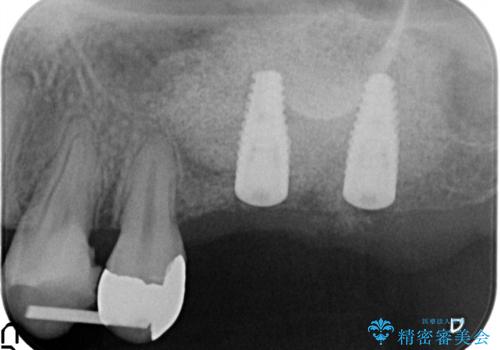

X線検査の結果、左上6には歯根破折、左上7には銀歯の下に大きな虫歯の再発が認められ共に抜歯をせずには症状の改善が見込めない状況です。

奥歯を2本失ったのち、しっかりと噛める環境へと整備するため、しっかりと骨の造成を行い清掃性を高めたインプラント治療を行っていくこととしました。

- 110万円(インプラント×2・チタンカスタムアバットメント×2・ジルコニアクラウン×2・仮歯×2・ 骨造成・サイナスリフト)費用は治療当時の料金となります